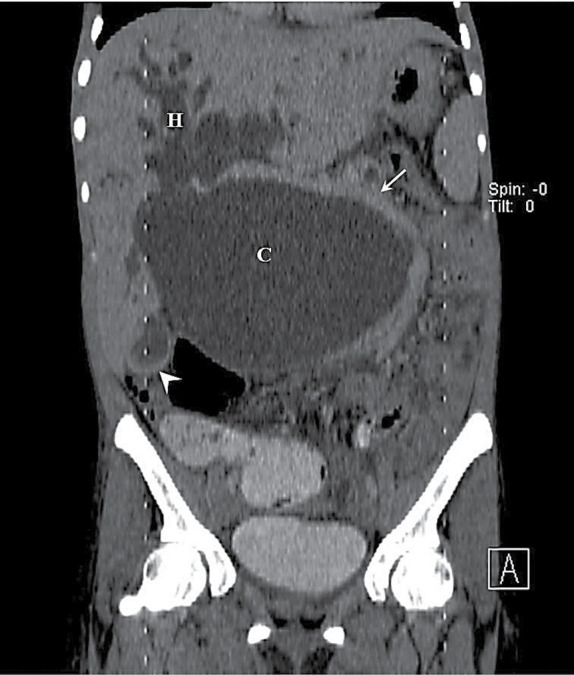

我们为您介绍一例 26 岁女性的病例,她出现了阻塞性黄疸和腹部肿胀。检查发现她患有巨大胆总管囊肿,并伴有梗阻性高胆红素血症。她接受了剖腹探查手术,引流并切除了胆总管囊肿,同时进行了 Roux-en-Y 肝空肠吻合术。随访 6 个月后,她的临床状况良好。

We present the case of a 26-year old woman who developed obstructive jaundice and massive abdominal swelling. Investigations revealed a huge choledochal cyst with obstructive pattern of hyperbilirubinaemia. She had exploratory laparotomy, drainage and excision of the choledochal cyst and Roux-en-Y hepaticojejunostomy. She has been followed up for 6 months in good clinical condition.